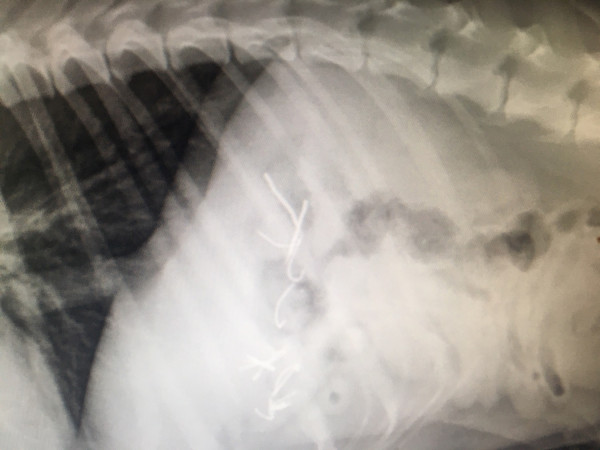

Εικόνες φρίκης στου Φιλοπάππου: 500 φόλες σε ακτίνα 2 χλμ - Έβαλαν αγκίστρια μέσα σε λουκάνικα

Εκατοντάδες φόλες γέμισε χθες ο λόφος του Φιλοπάππου, φόλες επικίνδυνες με τη μορφή μικρών λουκάνικων Φρανκφούρτης που έκρυβαν εντός τους αγκίστρια, βίδες και ρινίσματα. Το γεγονός πήρε μεγάλες διαστάσεις χάρις (και) στα post της Μάγιας Τσόκλη και της Έλενας Ακρίτα στο facebook, οι οποίες έχουν χιλιάδες followers στους λογαριασμούς τους.